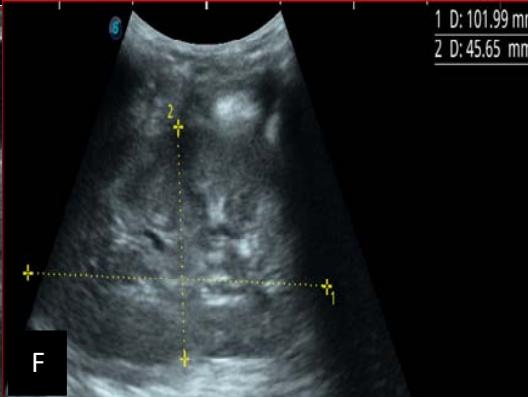

Figure 5: Abdominopelvic ultrasound control after 6 courses of chemotherapy in the same 3 year old patient with a ruptured left renal nephroblastoma; Images A, F, G, and H: show regression of the solid, endo and exo renal, left nephroblastoma mass treated with 6 courses of chemotherapy (current volume 430 ml vs) Images: B, C, and: show persistence of thrombotic permeation pan vena cava and ipsilateral renal. Image E: shows a volumetric regression of the intra-lesional hematic collection, at the tumor rupture estimated at 34.49 ml VS, Image I: represents the right kidney in B mode which is of normal echoculture. Source: Dr. Frederick Tshibasu Tshienda database.

Figure 6: 9-year-old sickle cell patient, referred for abdominal bloating with significant collateral venous circulation, in whom we noted: Image A: mass, Image B: healthy renal stump, inferior polar; Image C: left transmedian extension, Image D: thrombosis of the vena cava segments: supra, retro and sub hepatic, sparing a part of the supra hepatic vena cava segment over $30~\mathrm{mm}$. Image: Ascites of great abundance, Image F: normal left kidney, Image G: splenic microcalcifications, Image H: celiac adenopathy, Image I: sub pleural pulmonary nodules with the biggest measuring $3.88 \times 3.81 \mathrm{~mm}$, Image j: left pleurisy of great abundance. Source: Dr. Frederick Tshibasu Tshienda database.